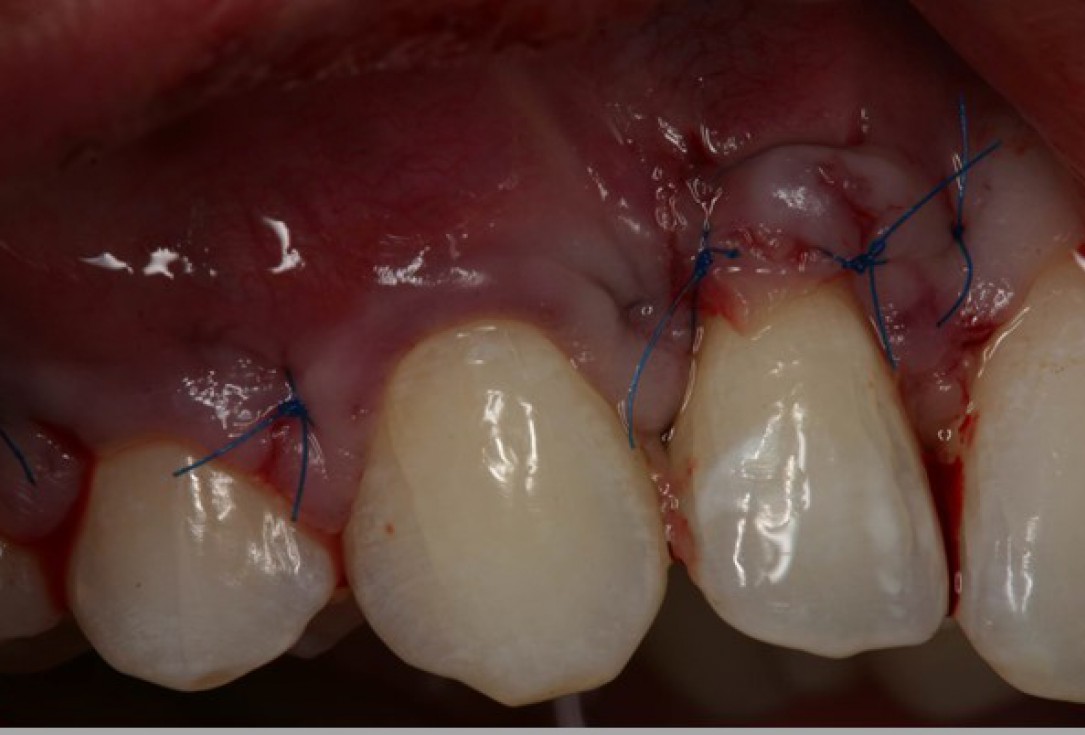

03/06 - Rehydrated and trimmed mucoderm® is placed over the denuded roots.Multiple gingival recessions treated with the modified coronally advanced flap in conjunction with mucoderm® - Prof. Dr. Dr. A. Kasaj

04/06 - The flap is repositioned in coronal direction to cover the root surfaces and the mucoderm® matrix completely.Multiple gingival recessions treated with the modified coronally advanced flap in conjunction with mucoderm® - Prof. Dr. Dr. A. Kasaj